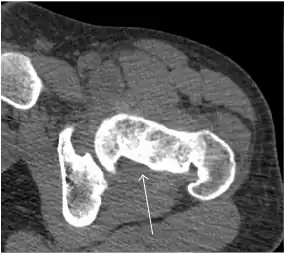

Synovial chondromatosis can be confidently diagnosed by X-ray when calcified cartilaginous chondromas are seen. However, other synovial proliferative processes, such as pigmented villonodular synovitis, require MRI for accurate diagnosis, although noncalcified synovitis can be suspected in radiographs by indirect signs, such as soft tissue swelling and/or erosions in the femoral head, femoral neck, or acetabulum (Figure 7).[1]

Figure 7:

-

Axial CT image of pigmented villonodular synovitis eroding the posterior cortex of the femoral neck.[1]

Sagittal T2* gradient echo image showing a posterior soft tissue mass with hypointense areas secondary to hemosiderin deposition.[1]

X-ray of synovial chondromatosis.[1]

CT of synovial chondromatosis.[1]

In synovial proliferative disorders, MRI demonstrates synovial hypertrophy. In the case of PVNS, characteristic foci of low signal intensity related to hemosiderin deposition are better seen on gradient echo T2* images (Figure 7). In the case of synovial osteochondromatosis, the synovial hypertrophy is accompanied by intermediate signal cartilaginous loose bodies and/or low signal calcified loose bodies.[1]